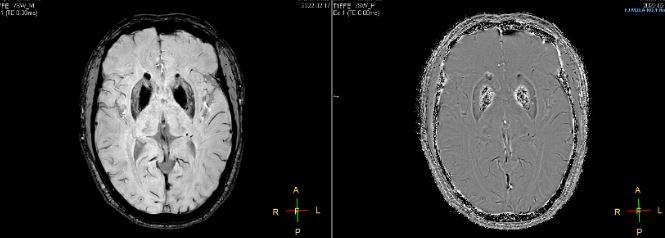

苍白球钙化的影像表现